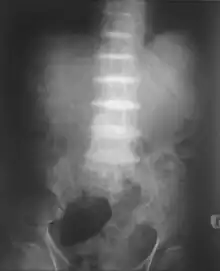

Alkaptonuria is a rare inherited genetic disease which is caused by a mutation in the HGD gene for the enzyme homogentisate 1,2-dioxygenase (EC 1.13.11.5); if a person inherits an abnormal copy from both parents (it is a recessive condition), the body accumulates an intermediate substance called homogentisic acid in the blood and tissues. Homogentisic acid and its oxidized form alkapton are excreted in the urine, giving it an unusually dark color. The accumulating homogentisic acid causes damage to cartilage (ochronosis, leading to osteoarthritis) and heart valves, as well as precipitating as kidney stones and stones in other organs. Symptoms usually develop in people over 30 years old, although the dark discoloration of the urine is present from birth.

After the age of 30, people begin to develop pain in the weight-bearing joints of the spine, hips, and knees. The pain can be severe to the point that interferes with activities of daily living and may affect the ability to work. Joint-replacement surgery (hip and shoulder) is often necessary at a relatively young age.[1] In the longer term, the involvement of the spinal joints leads to reduced movement of the rib cage and can affect breathing.[1] Bone mineral density may be affected, increasing the risk of bone fractures, and rupture of tendons and muscles may occur.[1]